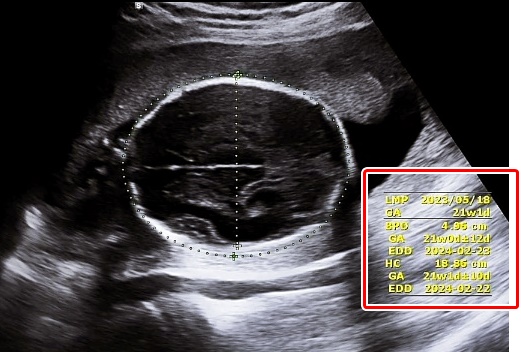

1. LMP (Last Menstrual Period): 최종월경일

마지막 생리 시작일을 의미합니다.

2. GA (Gestational Age): 임신기간, 임신주수

태아의 주수를 뜻하며 Ow Od (O week, O day), 주와 일수로 표기됩니다.

3. EDD (Estimated Due Date): 분만 예정일

GA를 바탕으로 산정된 분만 예정일입니다.

7. BPD (Biparietal Diameter): 머리직경

양쪽 옆통수 뼈와 뼈 사이의 길이를 말합니다.

8. HC (Head Circumference): 머리둘레

태아의 머리둘레입니다.